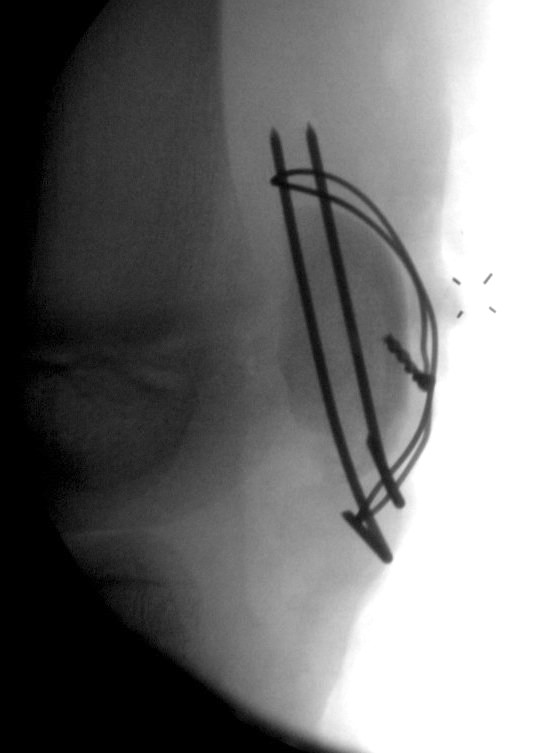

Displaced > 2 mm

ORIF

Technique

- intra-osseous sutures

- tension band wires

- suture anchors

Fixation of osteochondral fragment with headless compression screws, and sleeve fixation with sutures anchors

Patella sleeve ORIF with tension band wires